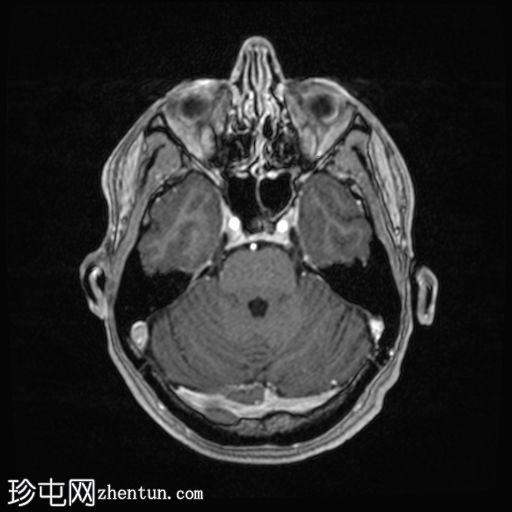

轴位

FLAIR

在轴位 FLAIR 上,左侧横窦-乙状窦交界处正常的暗流空隙消失,该空隙延伸至颈静脉孔内的颈内静脉。颅底下方左侧颈内静脉恢复正常的暗流空隙。然而,左侧横窦-乙状窦交界处和颈内静脉内有强化,提示 FLAIR 上存在缓慢血流,而非慢性强化血栓。